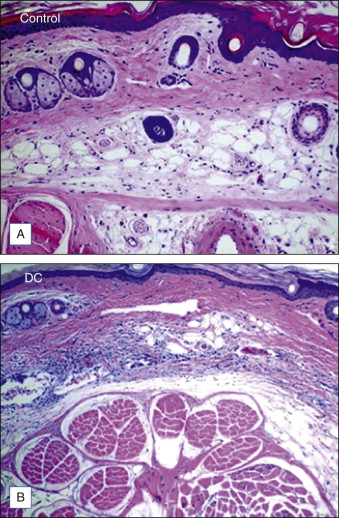

Subcutaneously injected DC leads to tissue necrosis as a result of its cytotoxic, detergent effects on the cellular membranes. In vivo and ex vivo animal or human tissue exposed to DC demonstrate fat cell lysis, fat, muscle, and collagen necrosis; erythrocyte extravasation; a mixed infiltrate consisting of polymorphonuclear leukocytes, lymphocytes, macrophages; multinucleated giant cells, and fibrosis.

As noted, in vitro, DC destroys nonadipose cells. Since it has the capacity to destroy nonadipose cells, we need to explain how it can be selective for adipose tissue ( Fig. 11.3 ). The ability of DC to lyse cells is inversely related to the amount of protein surrounding it and within tissue with which it comes into contact. The presence of albumin appears to inhibit the cell lysing activity of DC. Albumin is found in high concentrations in vital tissue but low concentrations in fat, which can explain why injections of low dose DC into fat are relatively safe clinically. This ‘safety valve’ effect of albumin on DC has fortunately made it an ideal candidate for subcutaneous fat injection.